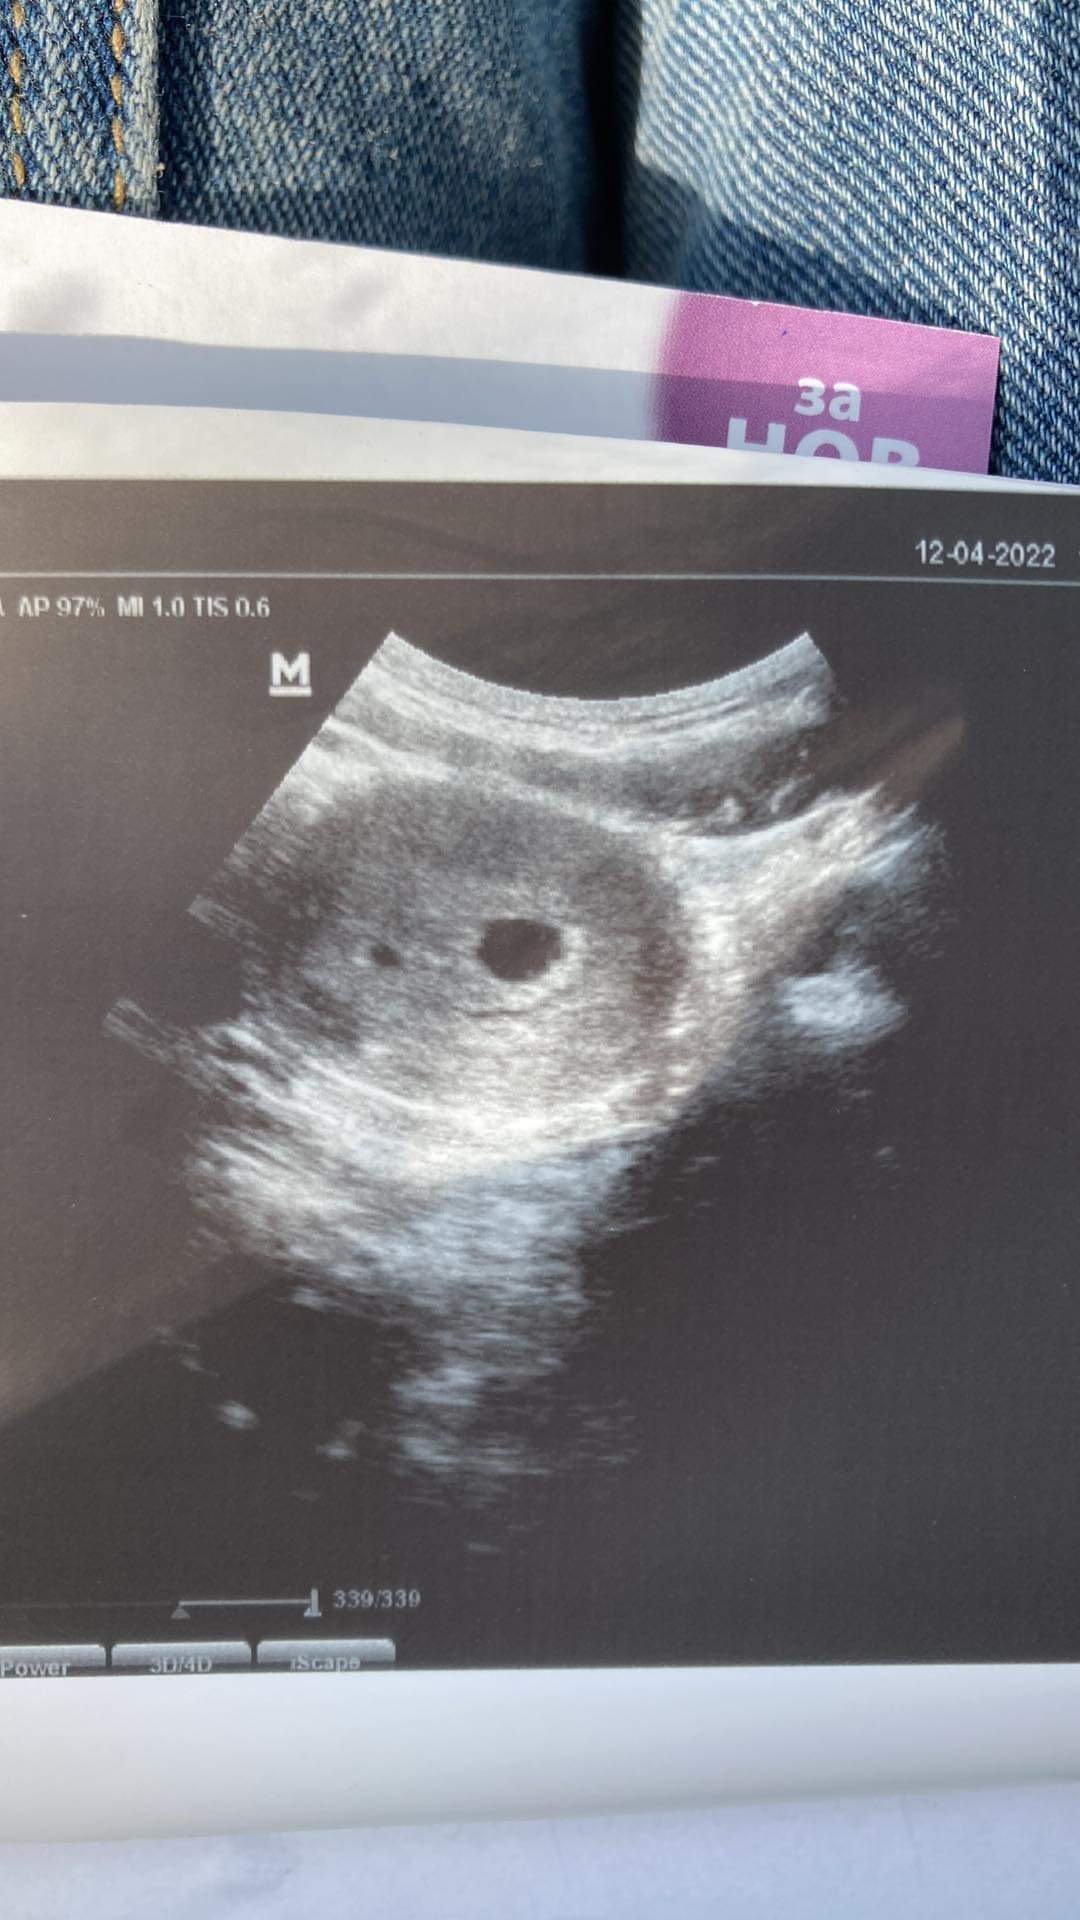

Днес звънях на доки да си запазя час за преглед в петък, но щял да пътува и ме извика днес следобяд!  Ще ви прикача снимка да видите и вие според вас дали има нещо странно 😀

Аз мисля че са два плодни сака ❤️❤️Супер 😉Blondy23 link=topic=1427428.msg44607804#msg44607804 date=1649785487]

Блонди две ли са Heart Eyes

Честно казано и аз това си помислих 😀 ама док каза, че нямало данни да е такова. Каза че било нещо от маточната лигавица 🤷♀ След 10 дни ме вика за регистрация. Според него съм в 4та седмица, а съм с 12 дни закъснение.. объркана работа, но и мен сега ме гложди дали са две? 😀